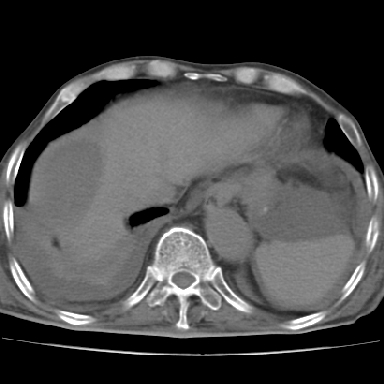

以下是引用qian在2006-12-4 19:11:00的发言:[br]胸腔和腹腔内均见有液性影,肝上极包膜下有一较大椭圆形低密度影,密度均匀,边缘清晰,结合病史考虑术后肝脓肿并胸腹腔积液。

以下是引用chry3在2006-12-4 21:05:00的发言:[br]应该往上扫几层,我考虑膈下脓肿。[br]大家考虑:胃部手术怎会造成肝内脓肿,隔下脓肿到是会造成的

以下是引用dyqct在2006-12-4 19:54:00的发言:[br]考虑:1、肝包膜下脓肿;[br] 2、少量腹水;[br] 3、右侧少量胸膜腔积液。